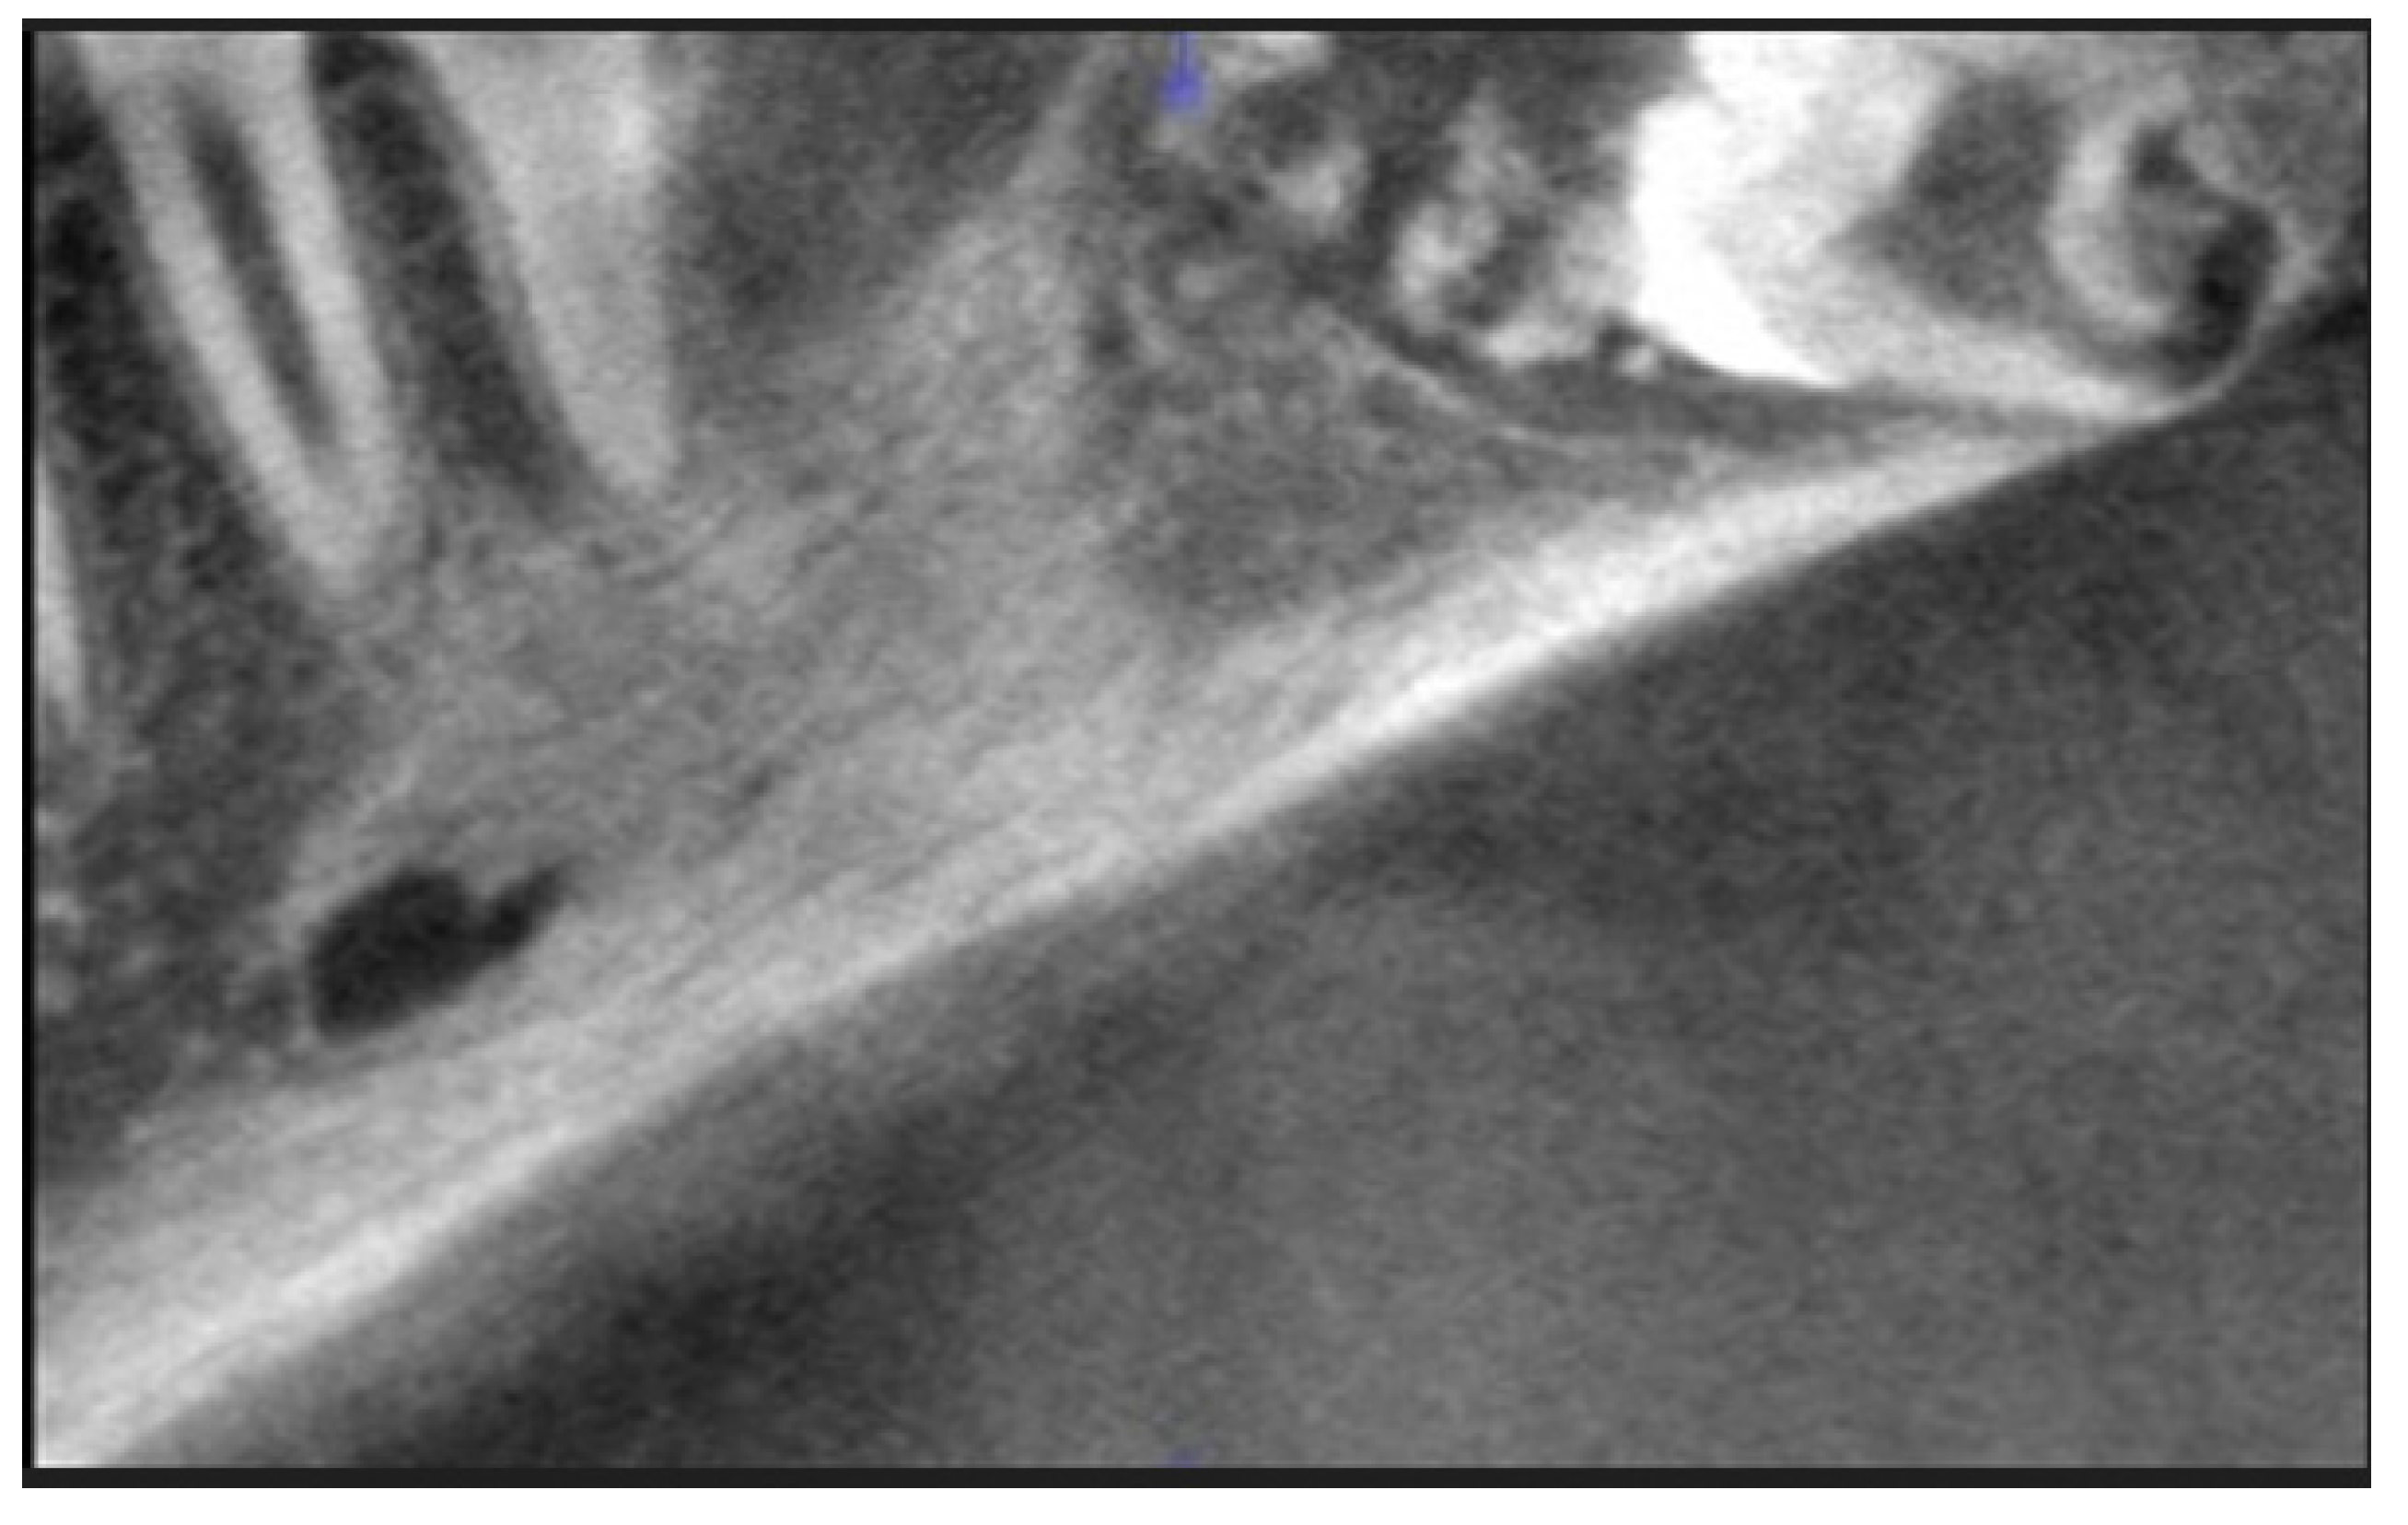

2. Case Report Presentation